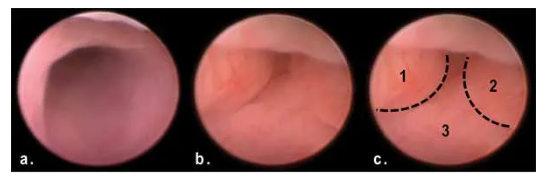

2. AOM/DSS造模50天后,與正常結(jié)腸(a)相比,模型組產(chǎn)生了多發(fā)性息肉樣腫塊阻塞末端結(jié)腸管腔(b、c)。

image.png